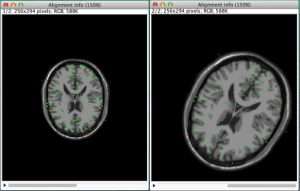

今回は、ImageJという画像解析ソフトを使って、画像位置合わせにトライしてみようと思います。 従来のImageJには、画像位置合わせの機能が搭載されていませんでした。ところが、ImageJは、Pluginとして自作した機能を追加することができるのです。今回は、弊社が開発・公開しているPluginの中で、画像位置合わせのPluginを使います。ImageJへのPluginのインストールについては、下記のリンクを参照してください。 今回は、脳MRI画像を縦、横にそれぞれ30(pixels)平行移動させた画像を元画像に位置合わせする、という操作を行ってみます。 図1は、Plugin(LPX reg...